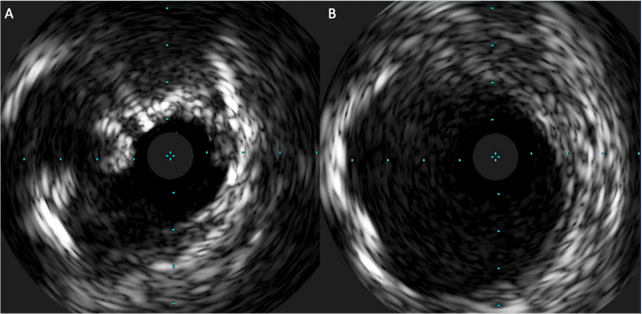

Right transfemoral access was used in 10 cases (77%) and left femoral in 3 (23%), according to the larger MLD as measured by CT analysis. In 4 cases (30.8%) with severe vessel tortuosity and presence of bulky and asymmetric calcifications confirmed at IVUS, PTA was initially performed with a smaller non-compliant balloon, compared to reference vessel diameter. The main reason for the choice of a less than 1:1 balloon to vessel ratio in such cases was the operator’s concern about vascular rupture.

Conversely, the remaining 9 cases (69.2%) were initially approached with a 1:1 sized non-compliant balloon, either measured at preoperative CT scan or reassessed during the procedure with intravascular ultrasound (IVUS). No oversizing (> 1:1 balloon to vessel ratio) was performed in any case.

Each patient underwent 4 to 6 inflations using non-compliant balloons with an average diameter and length of 6.4 ± 1.6 mm and 62 ± 14 mm, respectively. After initial PTA, IVUS re-check was used in 8 cases (61.5%), guiding the step-up to IVL when balloon waist was still present despite multiple inflations. Further attempts to deliver the valve immediately after PTA were not performed for these 8 patients, as IVUS findings already confirmed insufficient plaque modification. In the remaining 5 cases (38.5%), balloon inflation appeared to be satisfactory at the fluoroscopy; thus, delivery of the valve was unsuccessfully re-attempted immediately after PTA but before IVL.

In 9 cases (69.2%), the valve was successfully advanced immediately after IVL performance without the need of further balloon dilatation. In the remaining 4 cases (30.8%), additional inflations with non-compliant balloons were performed because of unsatisfactory lumen gain at either post-IVL angiogram or post-IVL IVUS.

Examples of a suboptimal result and a good result are displayed in Figure 5. None of the patients ended up receiving or requiring any stent placement along the iliofemoral axis. Overall, the mean procedural time was 134 ± 83 minutes, the mean fluoroscopy time was 37 ± 13 minutes, and the mean contrast volume was 125 ± 58 mL.